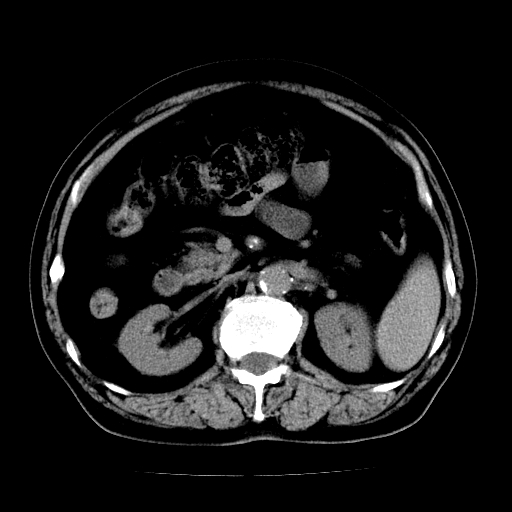

男,71岁,皮肤黄染四天。

肝内外胆管及胆总管上段扩张,考虑为梗阻所致,建议mrcp检查。

支持考虑胆总管癌并肝内外胆管扩张。 局部应薄扫。心包钙化。

胰腺上端胆总管内见软组织影,强化不明显,结合临床,还是考虑低位梗阻性黄疸,胆总管癌可能性大